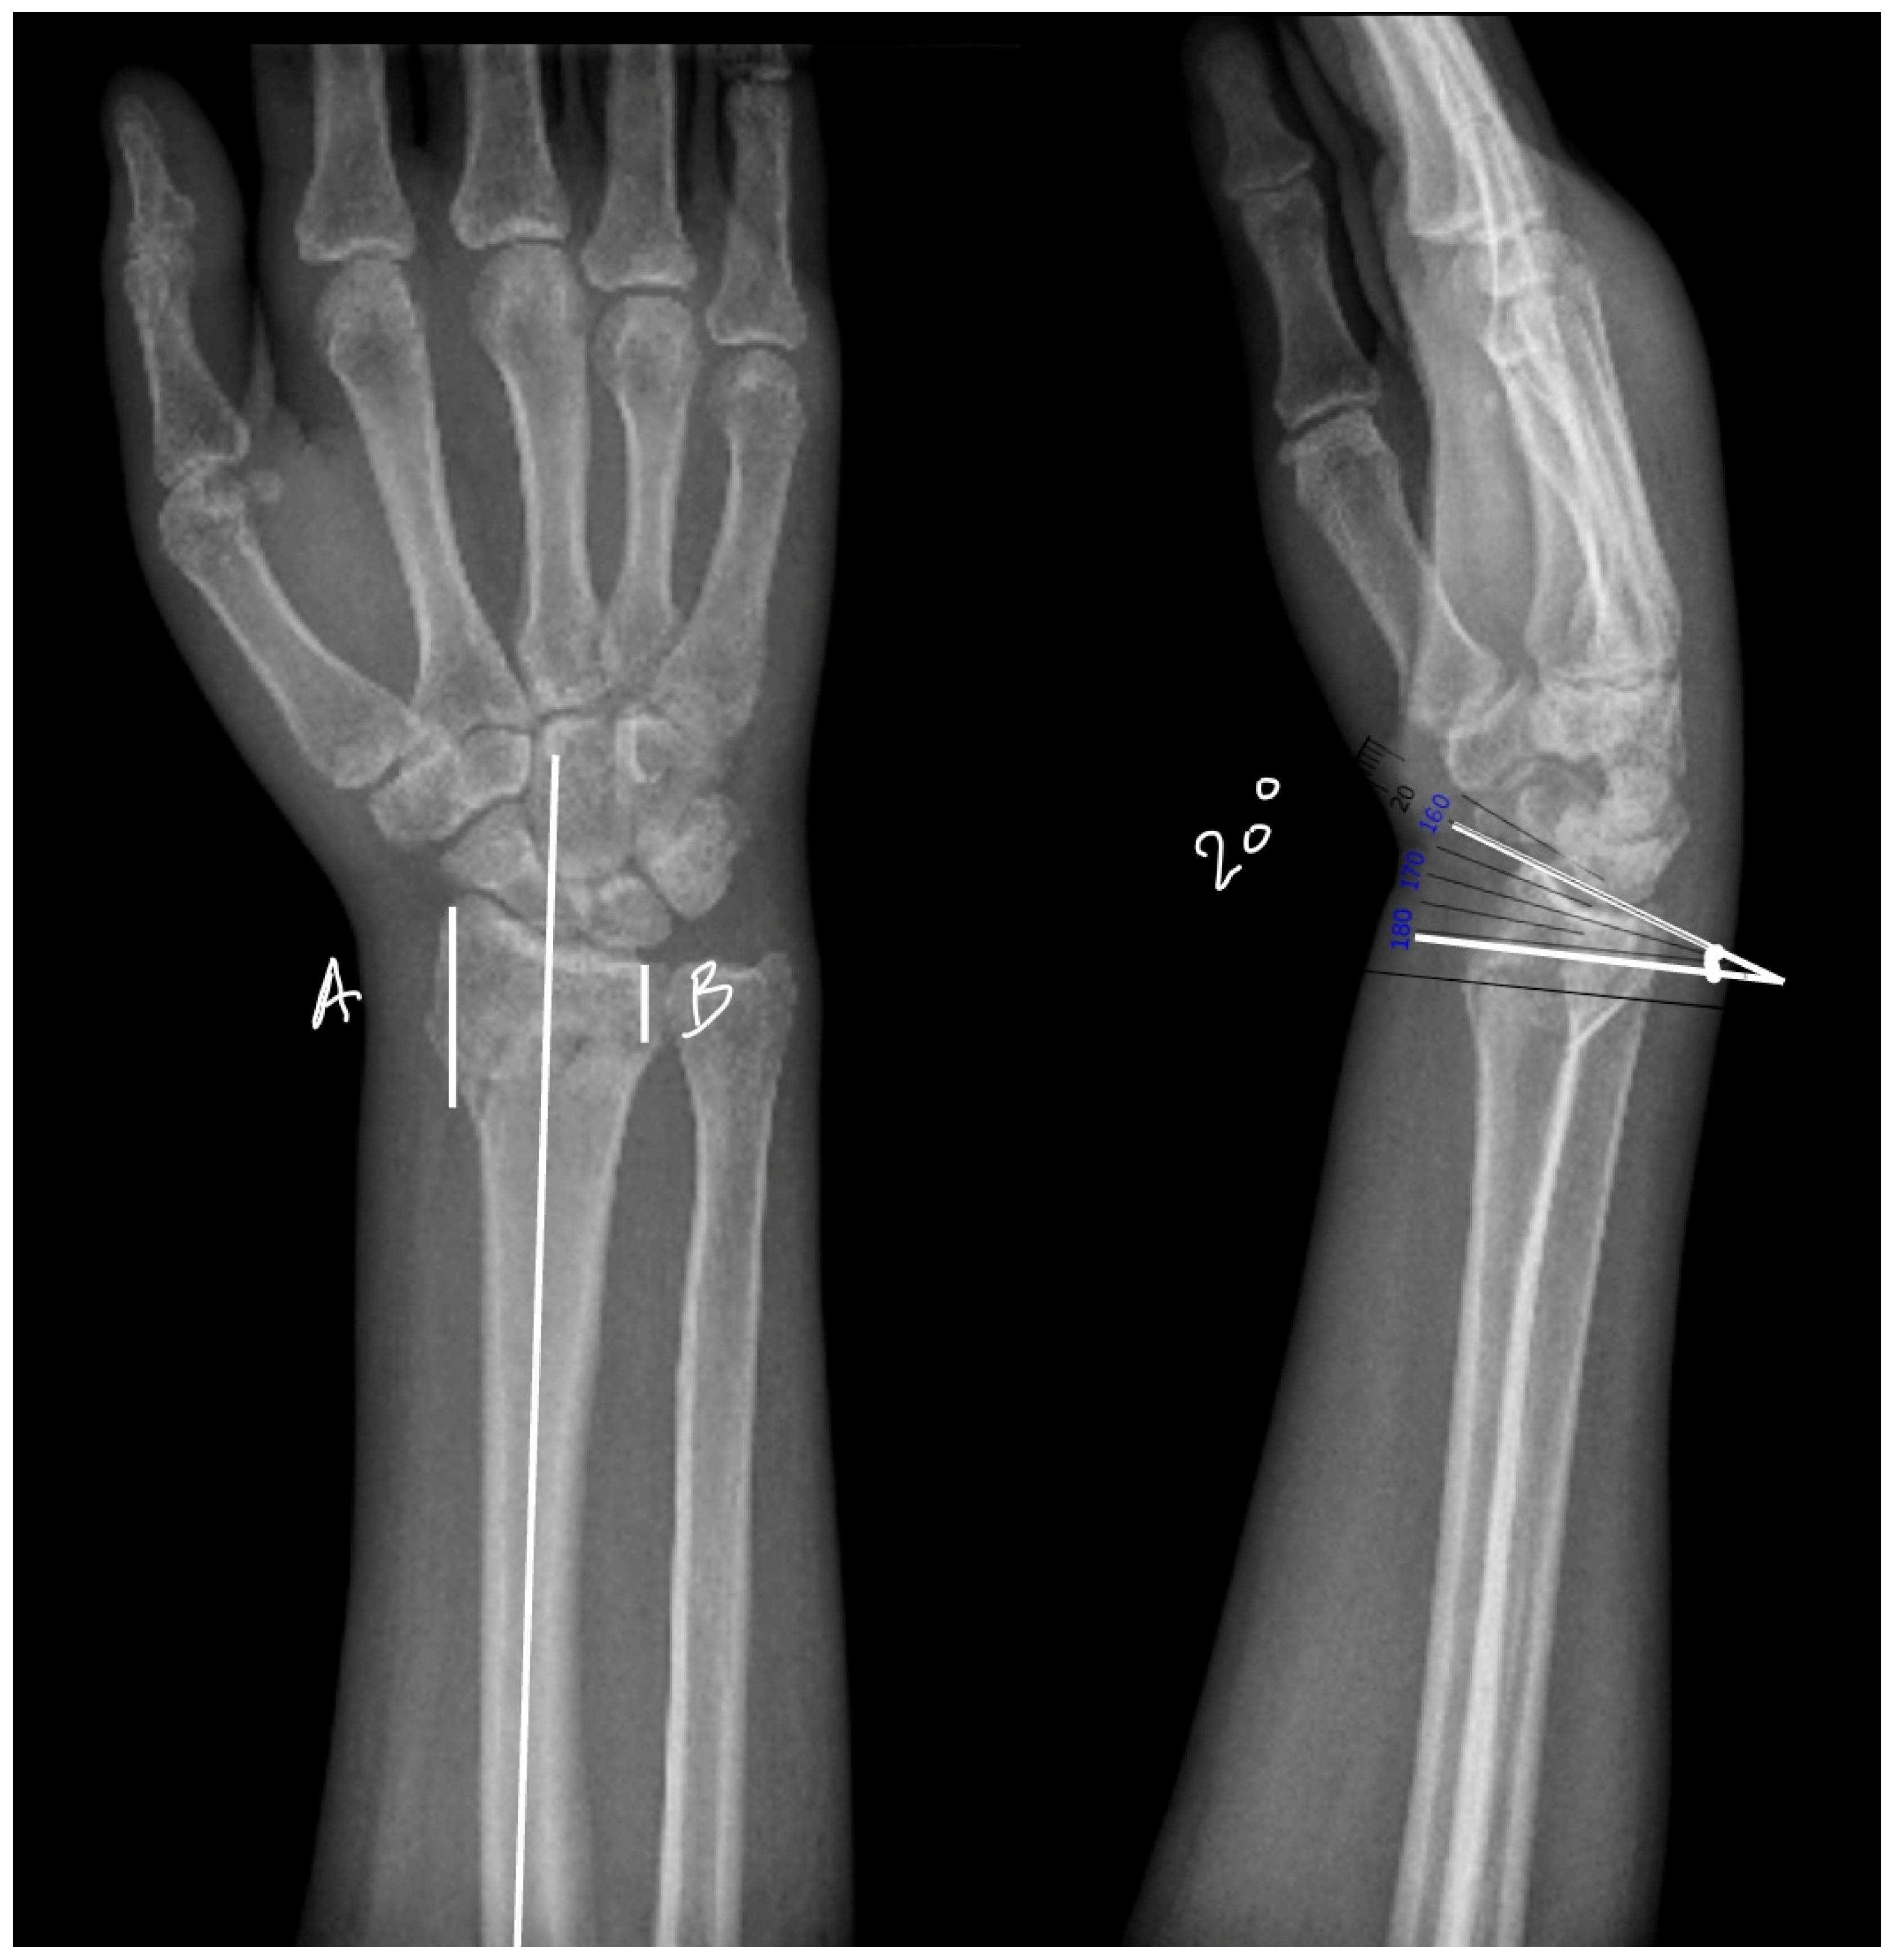

Two primary surgical techniques are commonly used to manage distal radius fractures (DRFs): open reduction with volar plates (Figure 1) and percutaneous fixation using Kirschner wires (K-wires) (Figure 2) [5]. While volar plates are frequently adopted for their advantages [6], K-wire fixation remains a viable alternative due to its reduced procedure duration and lower associated costs. However, there is ongoing debate regarding the optimal number, size, and configuration of K-wires necessary for effective fracture stabilization, with the biomechanical properties of various arrangements largely underexplored [5,7].

To ensure consistency and clinical relevance in the experimental model, preoperative radiographs of patients with extra-articular distal radius fractures were obtained from Romania, Iasi County emergency hospital “Sfântul Spiridon”. The X-rays were analyzed to determine the key anatomical parameters of the distal radius. In the anterior–posterior (AP) view, the distance from the articular surface to the fracture line was measured from both the medial and lateral borders of the radius with a mean between the two of 23.4 mm (±3.2 mm) (Figure 4). This measurement was used as a reference to guide the positioning of the fracture in the turkey bones.

Lateral radiographs were also used to measure the angle of the fracture relative to the radiocarpal joint, with a mean fracture angle of 19.7 degrees (±8.9 degrees). Using this information, a hand-held surgical saw was used to create fractures at an angle of approximately 20 degrees to the long axis of the bone, with the cuts positioned 20 mm from the distal articular surface, replicating typical clinical fracture patterns. Each K-wire was controlled to penetrate 60–70% of the cortical bone, leaving part of the bone structure intact to maintain stability during biomechanical testing.

Figure 4. Dorsally displaced distal radius fracture measurements on anteroposterior (AP) and lateral radiographs. On AP views, we can calculate (A) lateral side measurement of the fracture line distance from the articular surface, and (B) medial side measurement of the fracture line distance from the articular surface. And on lateral views, we can calculate the mean angle between the radiocarpal joint line and fracture line.